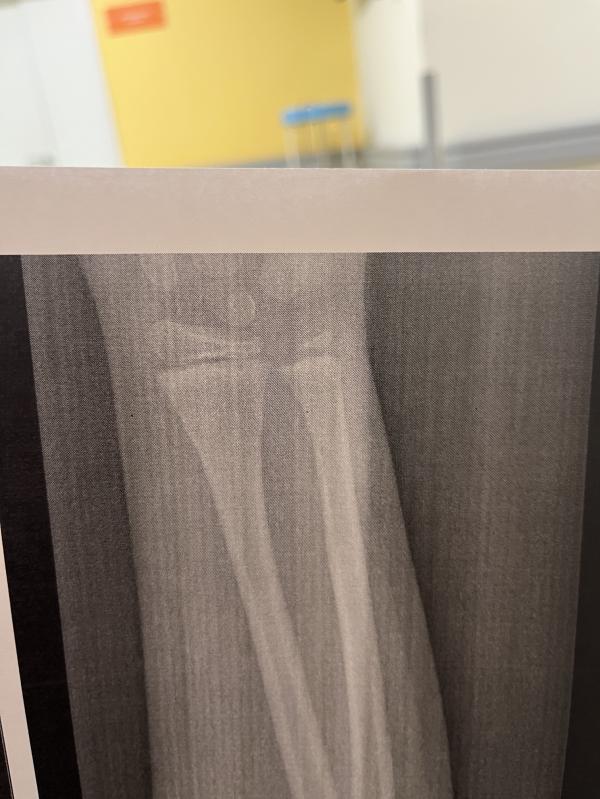

Болит ближе к кисти. Закрытый перелом нижней трети лучевой кости без смещения отломков.